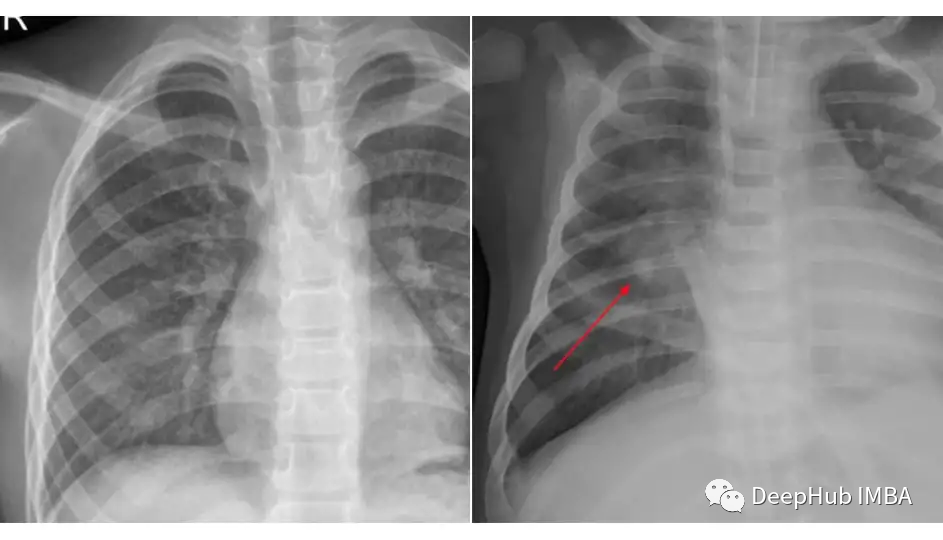

我们将使用来自Kaggle的胸部x光数据集进行肺炎分类来进行知识蒸馏的示例。我们使用的数据集被组织成3个文件夹(train, test, val),并包含每个图像类别的子文件夹(Pneumonia/Normal)。共有5,863张x射线图像(JPEG)和2个类别(肺炎/正常)。

比较一下这两个类的图片: